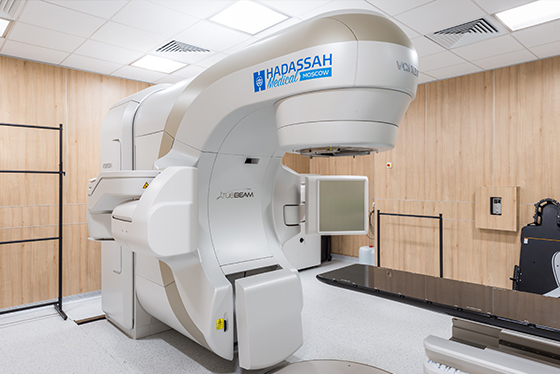

Лучевая терапия

Лучевая терапия (радиотерапия) — это применение ионизирующего излучения для лечения злокачественных новообразований. Схема лечения содержит в себе несколько циклов процедур, проводимых через определенные временные интервалы. Радиотерапия может назначаться как отдельно, так и совместно с хирургическим вмешательством.

Дистанционная лучевая терапия – наиболее оптимальный вариант. Подразумевает действие на опухоль излучения, исходящего из расположенного за пределами организма аппарата. Особый вид наружной дистанционной лучевой терапии — модулированная по интенсивности лучевая терапия (IMRT). IОна использует передовые технологии для точного направления лучей излучения на новообразование. IMRT значительно снижает вероятность поражения здоровых участков, минимизируя возможные негативные последствия.

Протонная терапия — разновидность наружной дистанционной лучевой терапии с применением протонов. Современная медицина практически не использует протонную терапию.

Брахитерапия – контактный метод радиотерапии с применением имплантов. По способу применения может быть ручной и автоматизированной.